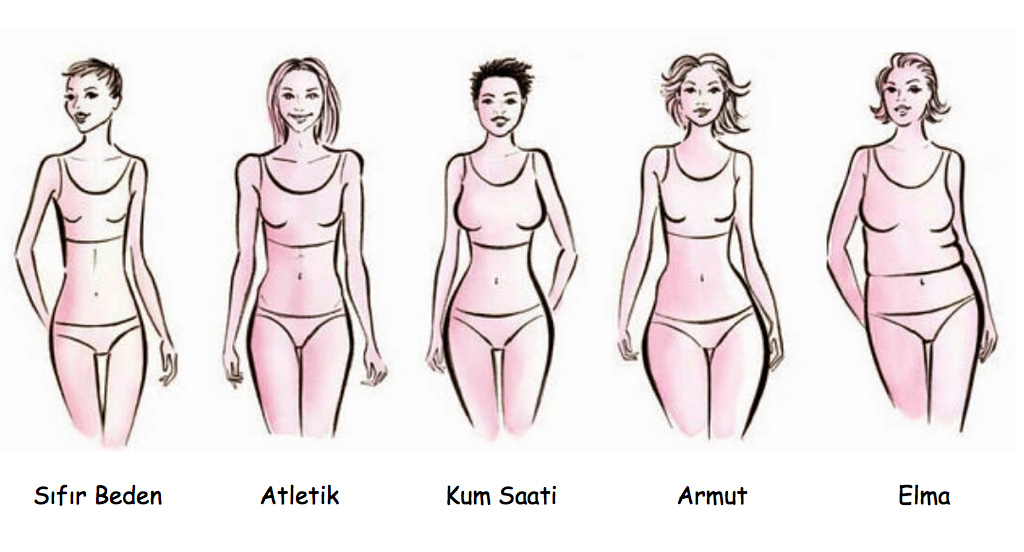

Armut Tipi Vucudu Olanlar Dikkat Saglik Haberleri Ntv

Kadinlarda Sik Gorulen Ama Az Bilinen Yag Dokusunun Agrili Odem Tablosu Lipodem Agrili Selulit Medicana Saglik Grubu

Kadinlarda Sik Gorulen Ama Az Bilinen Yag Dokusunun Agrili Odem Tablosu Lipodem Agrili Selulit Medicana Saglik Grubu